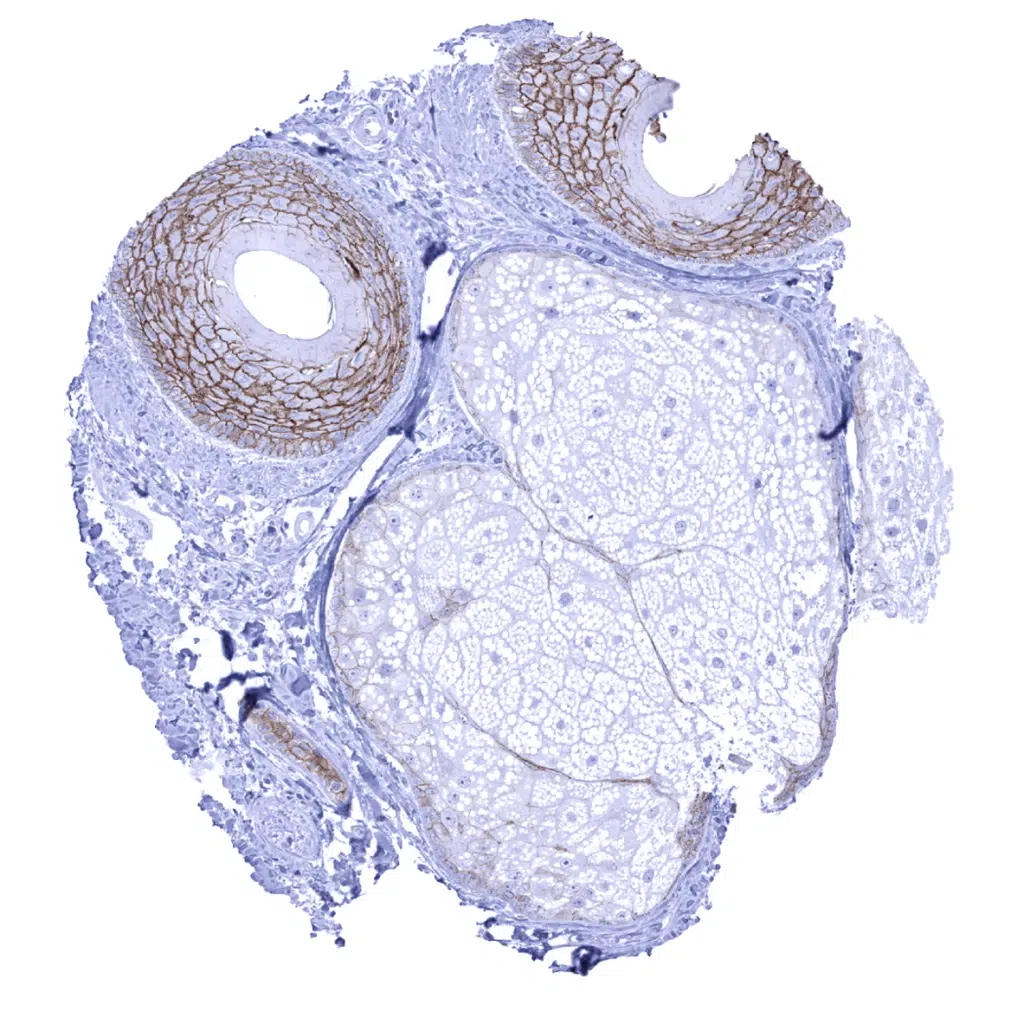

Skin – Moderate intensity Dsg3 immunostaining of basal and suprabasal epithelial cells.

Skin – Moderate to strong Dsg3 immunostaining of squamous epithelial epithelial cells of hair follicles.